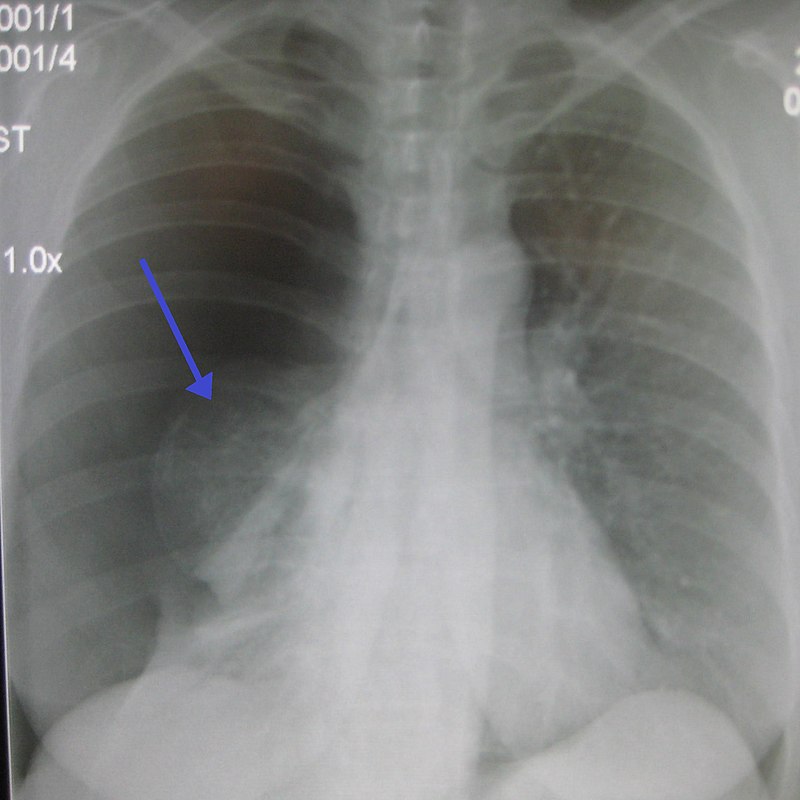

Pneumothorax is air buildup in the pleural space.

Pneumothorax leads to collapse of a portion of the lung.

The trachea shifts to the same side of the collapse.